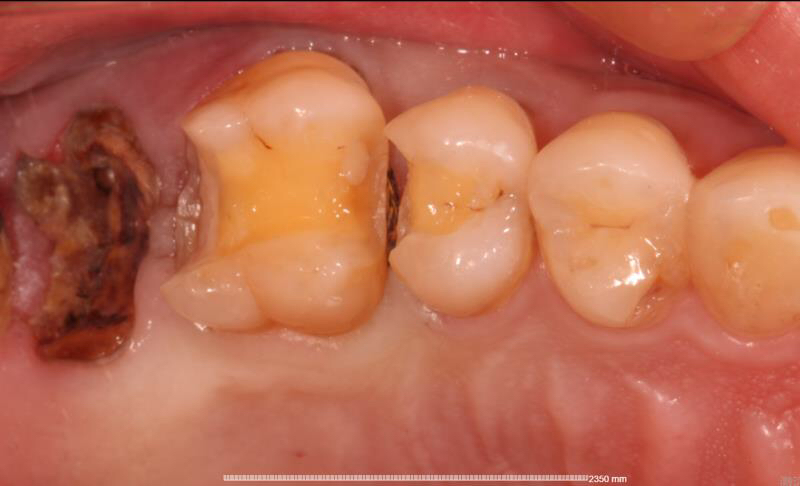

患者中年男性,右上5、6号牙邻接处龋坏,虽然表面没有明显龋坏,但釉质下可见低密度阴影,去龋过程中见釉质下大面积龋坏。由于龋坏面积较大,且位置处在邻接处,传统补牙强度较弱,所以我们建议这位患者采用嵌体修复的方式,一日就诊,一次搞定。

这种邻接龋坏多数是由于进食过后没有用牙线的习惯,食物嵌塞在2颗牙之间导致2颗牙都发生龋坏,卢医生建议大家要有进食过后使用牙线的习惯。